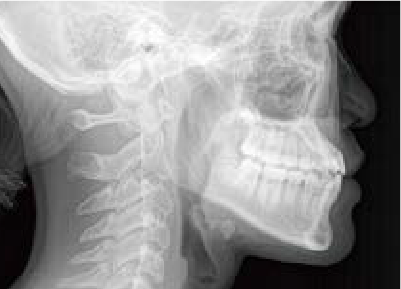

バイオブロック矯正とは

下方成長の症例のbefore/after

発達に寄り添いながら、

正しい成長を促す

バイオブロック矯正は、歯だけではなく顔全体の発達に焦点を当てた矯正治療法です。顎の下方成長(顎が下へ下がるように発達すること)を防ぐことに重点を置き、正しい方向への成長を促します。顎が正しく発達することで、永久歯が生える前に、生えやすい場所に移動するため、治療期間の短縮につながります。

取り外し可能な器具を使用して顎や歯の位置を正しい向きに調整し、より自然な方法で歯並びを整えることを目指します。

主要な治療内容と効果:顎の成長のコントロール

バイオブロック矯正では、顎の成長を前方へ導き、下顎の後退を防ぎます。

歯並びだけを整えるのではなく、すべての歯が自然な位置で並ぶことができる顎を目指します。

これは、成長過程だからこそできる治療法です。歯並びが崩れにくい顎をつくることで、問題の根本解決につながる上に後戻りしにくく、矯正後のケアも少なく済みます。